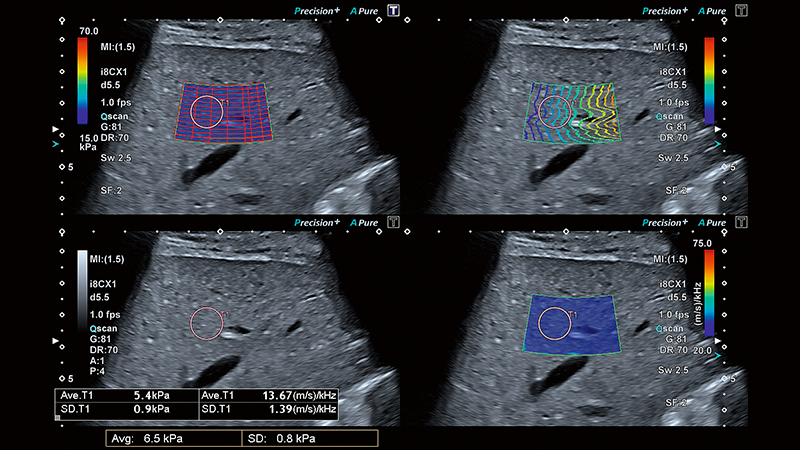

Залежно від ступеня фіброзу, паренхіма печінки демонструє підвищену віскоelasticity (в’язкопружність). Клініцисти досліджують жорсткість печінки як один із показників для діагностики фіброзу або цирозу печінки. Жорсткість печінки можна виміряти за допомогою еластографії зсувної хвилі (SWE).

Розумні карти допомагають візуалізувати поширення зсувної хвилі в режимі реального часу. Унікальна карта поширення від Canon – це потужний та інтуїтивно зрозумілий інструмент для візуальної оцінки якості еластограми.

Унікальний режим чотирьохканального перегляду Canon дозволяє одночасно порівняти швидкість, еластичність, поширення та дисперсію зсувної хвилі для більш повної та надійної оцінки стану печінки.